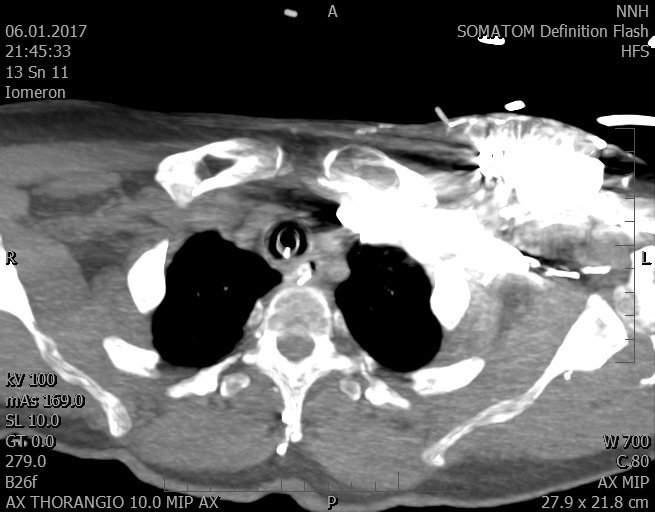

Video 2 - Echokardiograficky byla zjištěna těžká dysfunkce dilatační levé komory s nezvětšenou pravou komorou.Pro nejasnou příčinu zástavy jsme provedli i vyšetření výpočetní tomografií (CT), které vyloučilo plicní embolizaci (série 1 - soubory na konci článku). V den přijetí při přetrvávající oběhové nestabilitě byla nemocná opakovaně defibrilována pro fibrilaci komor se stabilizací rytmu po podání amiodaronu a mesocainu. Dle hemodynamických měření se jednalo o těžký kombinovaný šok. Vstupní laboratorní vyšetření bylo bez větších pozoruhodností. Posléze jsme doplnili anamnézu od příbuzných a zjistili, že pacientka užila do dvou hodin před srdeční zástavou první tabletu amoxicilinu na lehký respirační infekt. Při nevýtěžnosti vstupních vyšetření a nových anamnestických informacích jsme doplnili 14 hodin po kolapsu vyšetření koncentrace tryptázy v séru, která byla extrémně zvýšena (tabulka 2), což nás vedlo k podezření na anafylaxi.